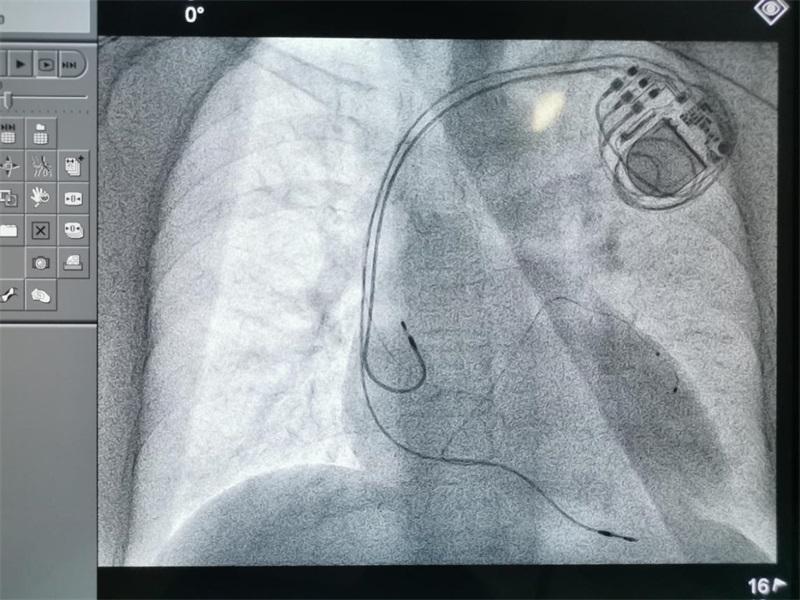

9月8日,南昌大學(xué)一附院心內(nèi)科團(tuán)隊(duì)為一名高危心力衰竭患者完成3D打印心臟模型指導(dǎo)下心臟再同步化治療(Cardiac Resynchronization Therapy,CRT)植入術(shù)。手術(shù)由王夢(mèng)洪教授、彭景添教授、彭小平教授共同完成,該手術(shù)的成功開(kāi)展,標(biāo)志著該院院心內(nèi)科治療技術(shù)再上新臺(tái)階。

術(shù)前,彭小平教授積極與影像科聯(lián)系、溝通,根據(jù)患者心臟CT圖像三維重建,通過(guò)3D打印技術(shù),立體展示冠狀靜脈各分支以及心腔的空間結(jié)構(gòu),重建帶有冠狀靜脈分支的心臟立體模型,精確指導(dǎo)左、右心室電極、心房電極植入位置。手術(shù)過(guò)程中,術(shù)者在3D打印心臟模型精準(zhǔn)指導(dǎo)下,將左室冠狀竇電極精準(zhǔn)定位于冠狀靜脈左室外膜面分支,右室螺旋電極及心房電極分別定位于右室心尖部及右心耳,最后連接起搏脈沖發(fā)射器。因有了3D打印心臟模型的指導(dǎo),手術(shù)較平時(shí)手術(shù)較少了近30分鐘。

該院心內(nèi)科彭小平教授等人的最新研究發(fā)現(xiàn),左、右心室電極植入位置間距離與CRT效果相關(guān),CRT術(shù)中左、右心室電極植入位置越大,相應(yīng)臨床效果越佳,左、右心室電極植入位置間距離是 CRT 效果獨(dú)立影響因素,此項(xiàng)研究成果獲2019年我院臨床優(yōu)秀新技術(shù)一等獎(jiǎng)。但是電極在冠狀靜脈分支、心室、心房的精確定位是影響CRT手術(shù)效果的重要因素,特別是如何在術(shù)前重建冠狀靜脈竇及其分支走形顯得尤其重要。

“3D打印心臟模型不僅可以重建心房心室,而且可以清晰顯示心臟冠狀竇及其分支血管的走形,為術(shù)中尋找合適的電極位置提供了極大的幫助,將有助于縮短手術(shù)時(shí)間,提高手術(shù)的安全性和成功率,提高術(shù)后CRT反應(yīng)性及療效?!迸硇∑浇淌诮榻B道。